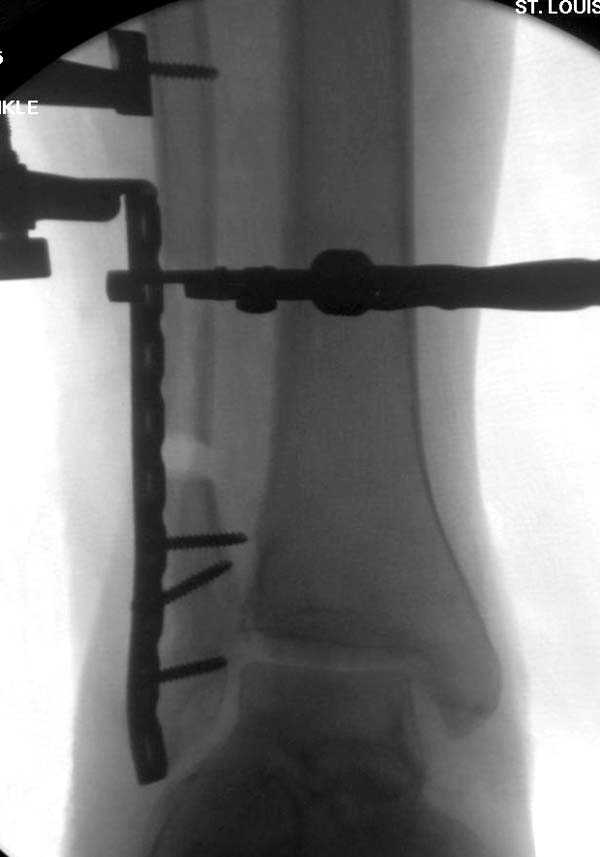

Здесь представлено решение похожей проблемы. Больной в течение года лечился консервативными мерами, и боли в голеностопе были основным показанием к операции.

Проведена обычная стандартная процедура по исправлению неудовлетворительного состояния голеностопного сустава, где кроме удлинения малоберцовой с применением compression tension device за проксимальный конец пластины, проведено замещение трикортикальным графтом из крыла, освобождение синдесмоза и медиальной щели от

фибротических масс с фиксацией.